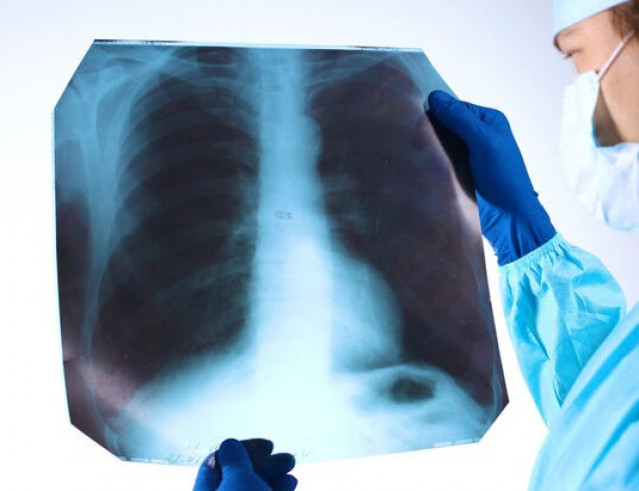

Абсцесс легкого: причины, симптомы, диагностика и лечение

Абсцесс легкого – заболевание, при котором в легочной ткани формируется полость, заполненная гноем. Это состояние требуе.....